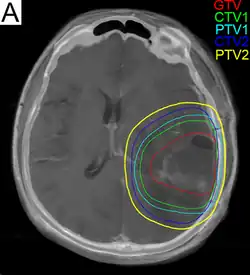

Radiation treatment planning for glioblastoma. GTV: gross tumor volume, CTV: clinical target volume, PTV: planning target volume.

Subsequent to surgery, radiotherapy becomes the mainstay of treatment for people with glioblastoma. It is typically performed along with giving temozolomide.[10] A pivotal clinical trial carried out in the early 1970s showed that among 303 GBM patients randomized to radiation or best medical therapy, those who received radiation had a median survival more than double those who did not.[77] Subsequent clinical research has attempted to build on the backbone of surgery followed by radiation. Whole-brain radiotherapy does not improve when compared to the more precise and targeted three-dimensional conformal radiotherapy.[78] A total radiation dose of 60–65 Gy has been found to be optimal for treatment.[79]